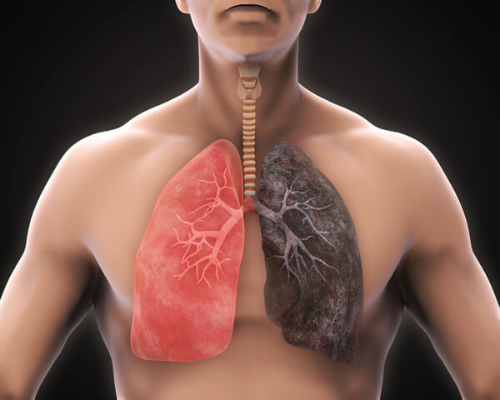

역류성 식도염 증상 8. 폐렴 증상

폐렴 증상은 역류성 식도염 증상 중 한 가지입니다. 역류성 식도염과 폐렴은 연관성이 없어 보일 수 있지만, 위산이 식도를 타고 올라가 폐를 자극하면 폐렴이 생길 수 있습니다. 폐가 감염되고 폐렴 증상이 계속해서 나타나면 역류성 식도염을 고려해야 합니다.